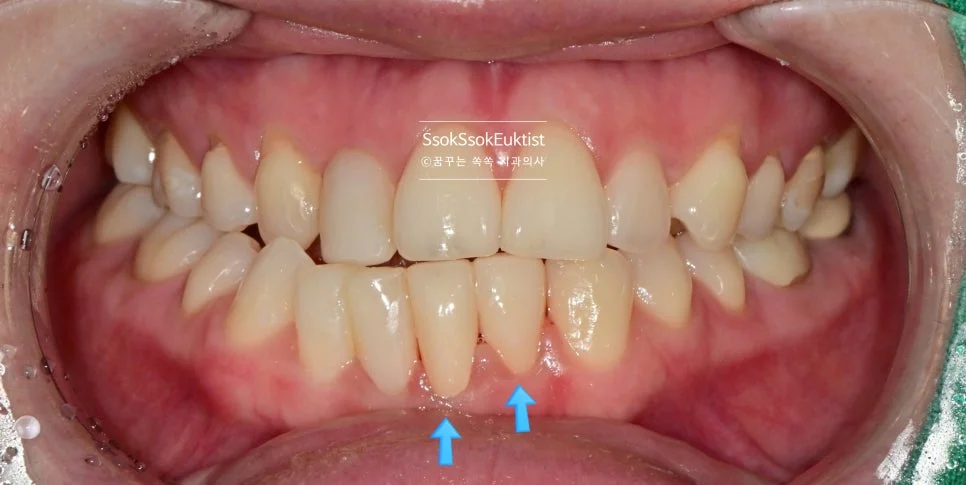

하악 교합면 사진 — 가장 전방에 위치한 치아 (화살표)

아래 앞니를 더 앞으로 뺄 필요는 없는 상황이었기에 라미네이트가 적합하지 않습니다!

가지런하지 않은 아래 앞니 (화살표) — 크라운 치료가 필요한 상태

모양과 위치를 드라마틱하게 개선하기 위해서는 크라운 치료가 필요하였고, 두 개 치아의 크라운 치료를 계획합니다. 그것도 신경치료 없이!!